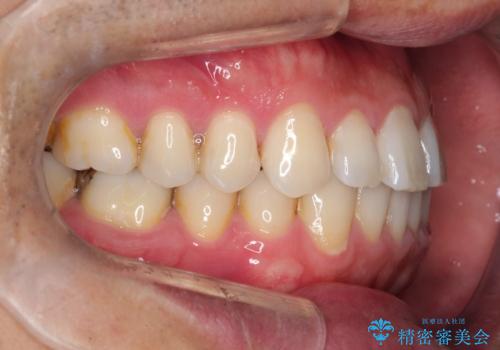

- 前歯の隙間を主訴に来院されました。

マウスピース矯正にて、隙間を綺麗に閉じることができ満足していただきました。

前歯の隙間を閉じる際は、前歯部の突き上げが懸念されるため、適切な治療計画が必要となります。